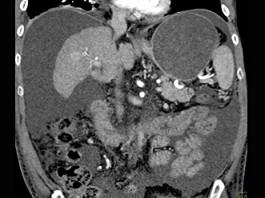

下列图像最可能的诊断是 ( )A.肝脓肿B.肝囊肿C.肝血管瘤D.原发性肝癌E.肝炎肝硬化

问题 下列图像最可能的诊断是 ( )

选项 A.肝脓肿 B.肝囊肿 C.肝血管瘤 D.原发性肝癌 E.肝炎肝硬化

答案 E